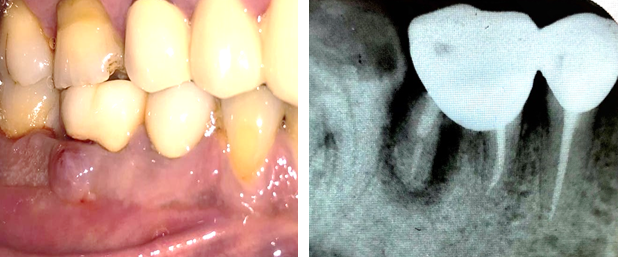

A 45 year old male patient reported to the department with the chief complaint of pain, food impaction, and pus discharge in the lower right posterior tooth .On clinical examination, a metal ceramic bridge was present connecting 46 and 45 and , abscess was present irt 46. A diagnostic radiograph reveals that 46 and 45 was root canal treated but the distal root of 46 was underobturated. Severe vertical bone loss was evident surrounding the distal root of 46 and involves the furcation area. The bone support of mesial root was completely intact. Tooth was tender on percussion with a deep periodontal pocket of 9 –10 mm on distal root of 46 region. Interproximal bone loss was seen between 46 and 47. Treatment options included extraction of 46 alone by preserving 45 followed by placement of implant later on 46, new fixed partial denture including 47 or removable partial denture. Patient did not wish to have the tooth removed, so conservative treatment option of root amputation and its pros and cons was explained. Patient happily opted the choice which included root amputation of the distal root of 46 by preserving the FPD.

The sutures were removed after 15 days. Betadine and saline irrigation done. The surgical site exhibited good healing. No postoperative complications were noticed. There was no swelling or any exaggerated pain or discomfort as reported by the patient. The soft tissue had collapsed in the distal aspect leaving a space of more than 3 mm apical to the crown, making it self-cleansable. Oral hygiene instructions and touch to teach brushing technique was advised. The patient was advised to use a interproximal brush to keep it clean. Radiographically some evidence of bone formation was noticed distal to mesial root during one month review

The patient reported after one year and the resected tooth exhibited no sign of gingival inflammation and shows excellent healing. Soft tissue covered the interdental area. No food impaction was present. The intraoral periapical radiograph depicted clear picture of regenerated bone in relation to the mesial root and on the extracted socket of 46.